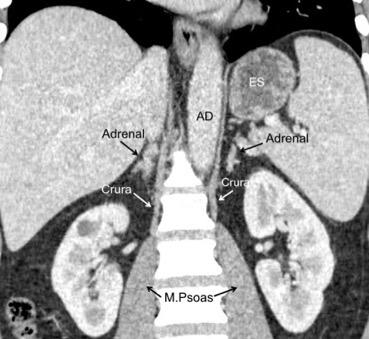

Parte lumbar: 1.Ligamentos arcuatos medial y lateral

2. Cruras conectadas a vértebras lumbares y discos. L1-3 a la dcha. L1-2 a la izda.

Cruras conectadas por encima del tronco celíaco por ligamento fibroso arcuato medial. Panicek DM et al. Radiographics. 1998

Las fibras más bajas de las cruras se funden con las de las vainas de los músculos psoas, acotando un espacio llamado “Espacio abierto de la vaina del psoas”, que comunica las cavidades torácica y abdominal.

Panda A et al. “Straddling Across Boundaries”. Thoracoabdominal Lesions: Spectrum and Pattern Approach. Curr Probl Diagn Radiol, 2015 /Restrepo CS et al. The diaphragmatic crura and retrocrural space: normal imaging appearance, variants, and pathologic conditions. Radiographics 2008